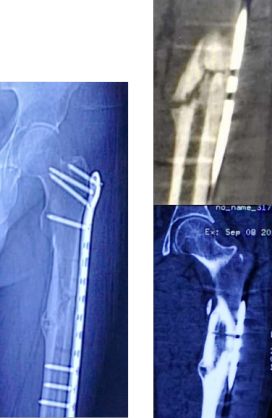

髓内钉与骨的过度处应力集中

应力集中断裂。内固定过于坚强,钉子粗,钢板与过度处应力集中(没有必要手术,必须手术可以用随内针加石膏固定)。

应力集中,一旦断裂很难愈合。髋强直邻近骨折最好方法是关节置换,缓解应力集中同时做接骨手术